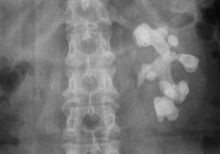

肺出血-肾炎综合征--切片